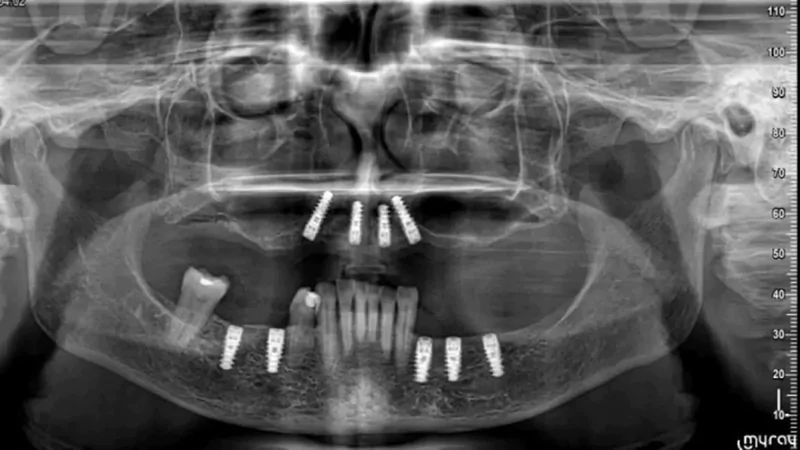

Since year 2000 we are Centre of excellence in implantology .We have done thousands of full mouth dental implant cases in last 25 years .We have a team approach where experienced implant surgeons , prosthodontists , maxillofacial surgeons , digital restorative dentists and lab technicians work together to deliver world class fixed teeth. We use multiple implant option from case to case. Some need All-on-4, some need All-on-6 or All-on-8 in selective cases.

All-on-6 Implants

It is an advanced technique in which six implants support a full arch of teeth. It ensures superior stability, durability, and improved chewing function.